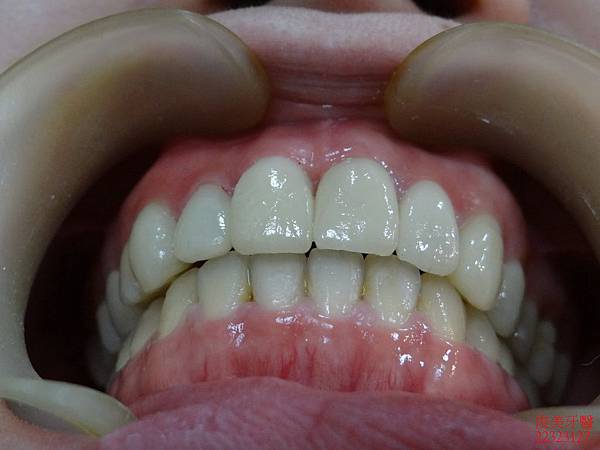

裝上新牙齒囉!!

最後將前牙的蛀牙及咬裂的部份一併修復,採用全瓷美白貼片一次到位,

兼具美觀及保護牙齒的神經喔!!牙齒也恢復為正常的牙弓形狀。

完美到一個不行........

療程結束後咬合良好。

牙縫不會直接嵌塞食物。

變身為超完美牙齒!!只能狂按"讚"啦~~~~~~~